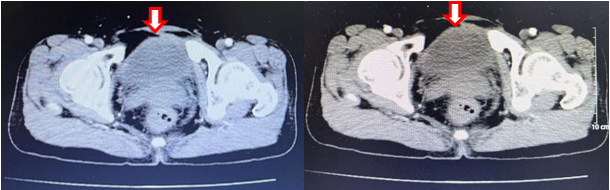

- Cắt lớp vi tính ổ bụng:

Hình 6: Cắt lớp vi tính ổ bụng (16/06/23): không thấy các tổn thương thứ phát tại bàng quang (mũi tên)

Hình 7: Cắt lớp vi tính ổ bụng (16/06/23): Hình ảnh u máu gan phải, khối lớn nhất kích thước 35x38mm (không thay đổi đáng kể so với phim cũ 06/2022) (mũi tên)